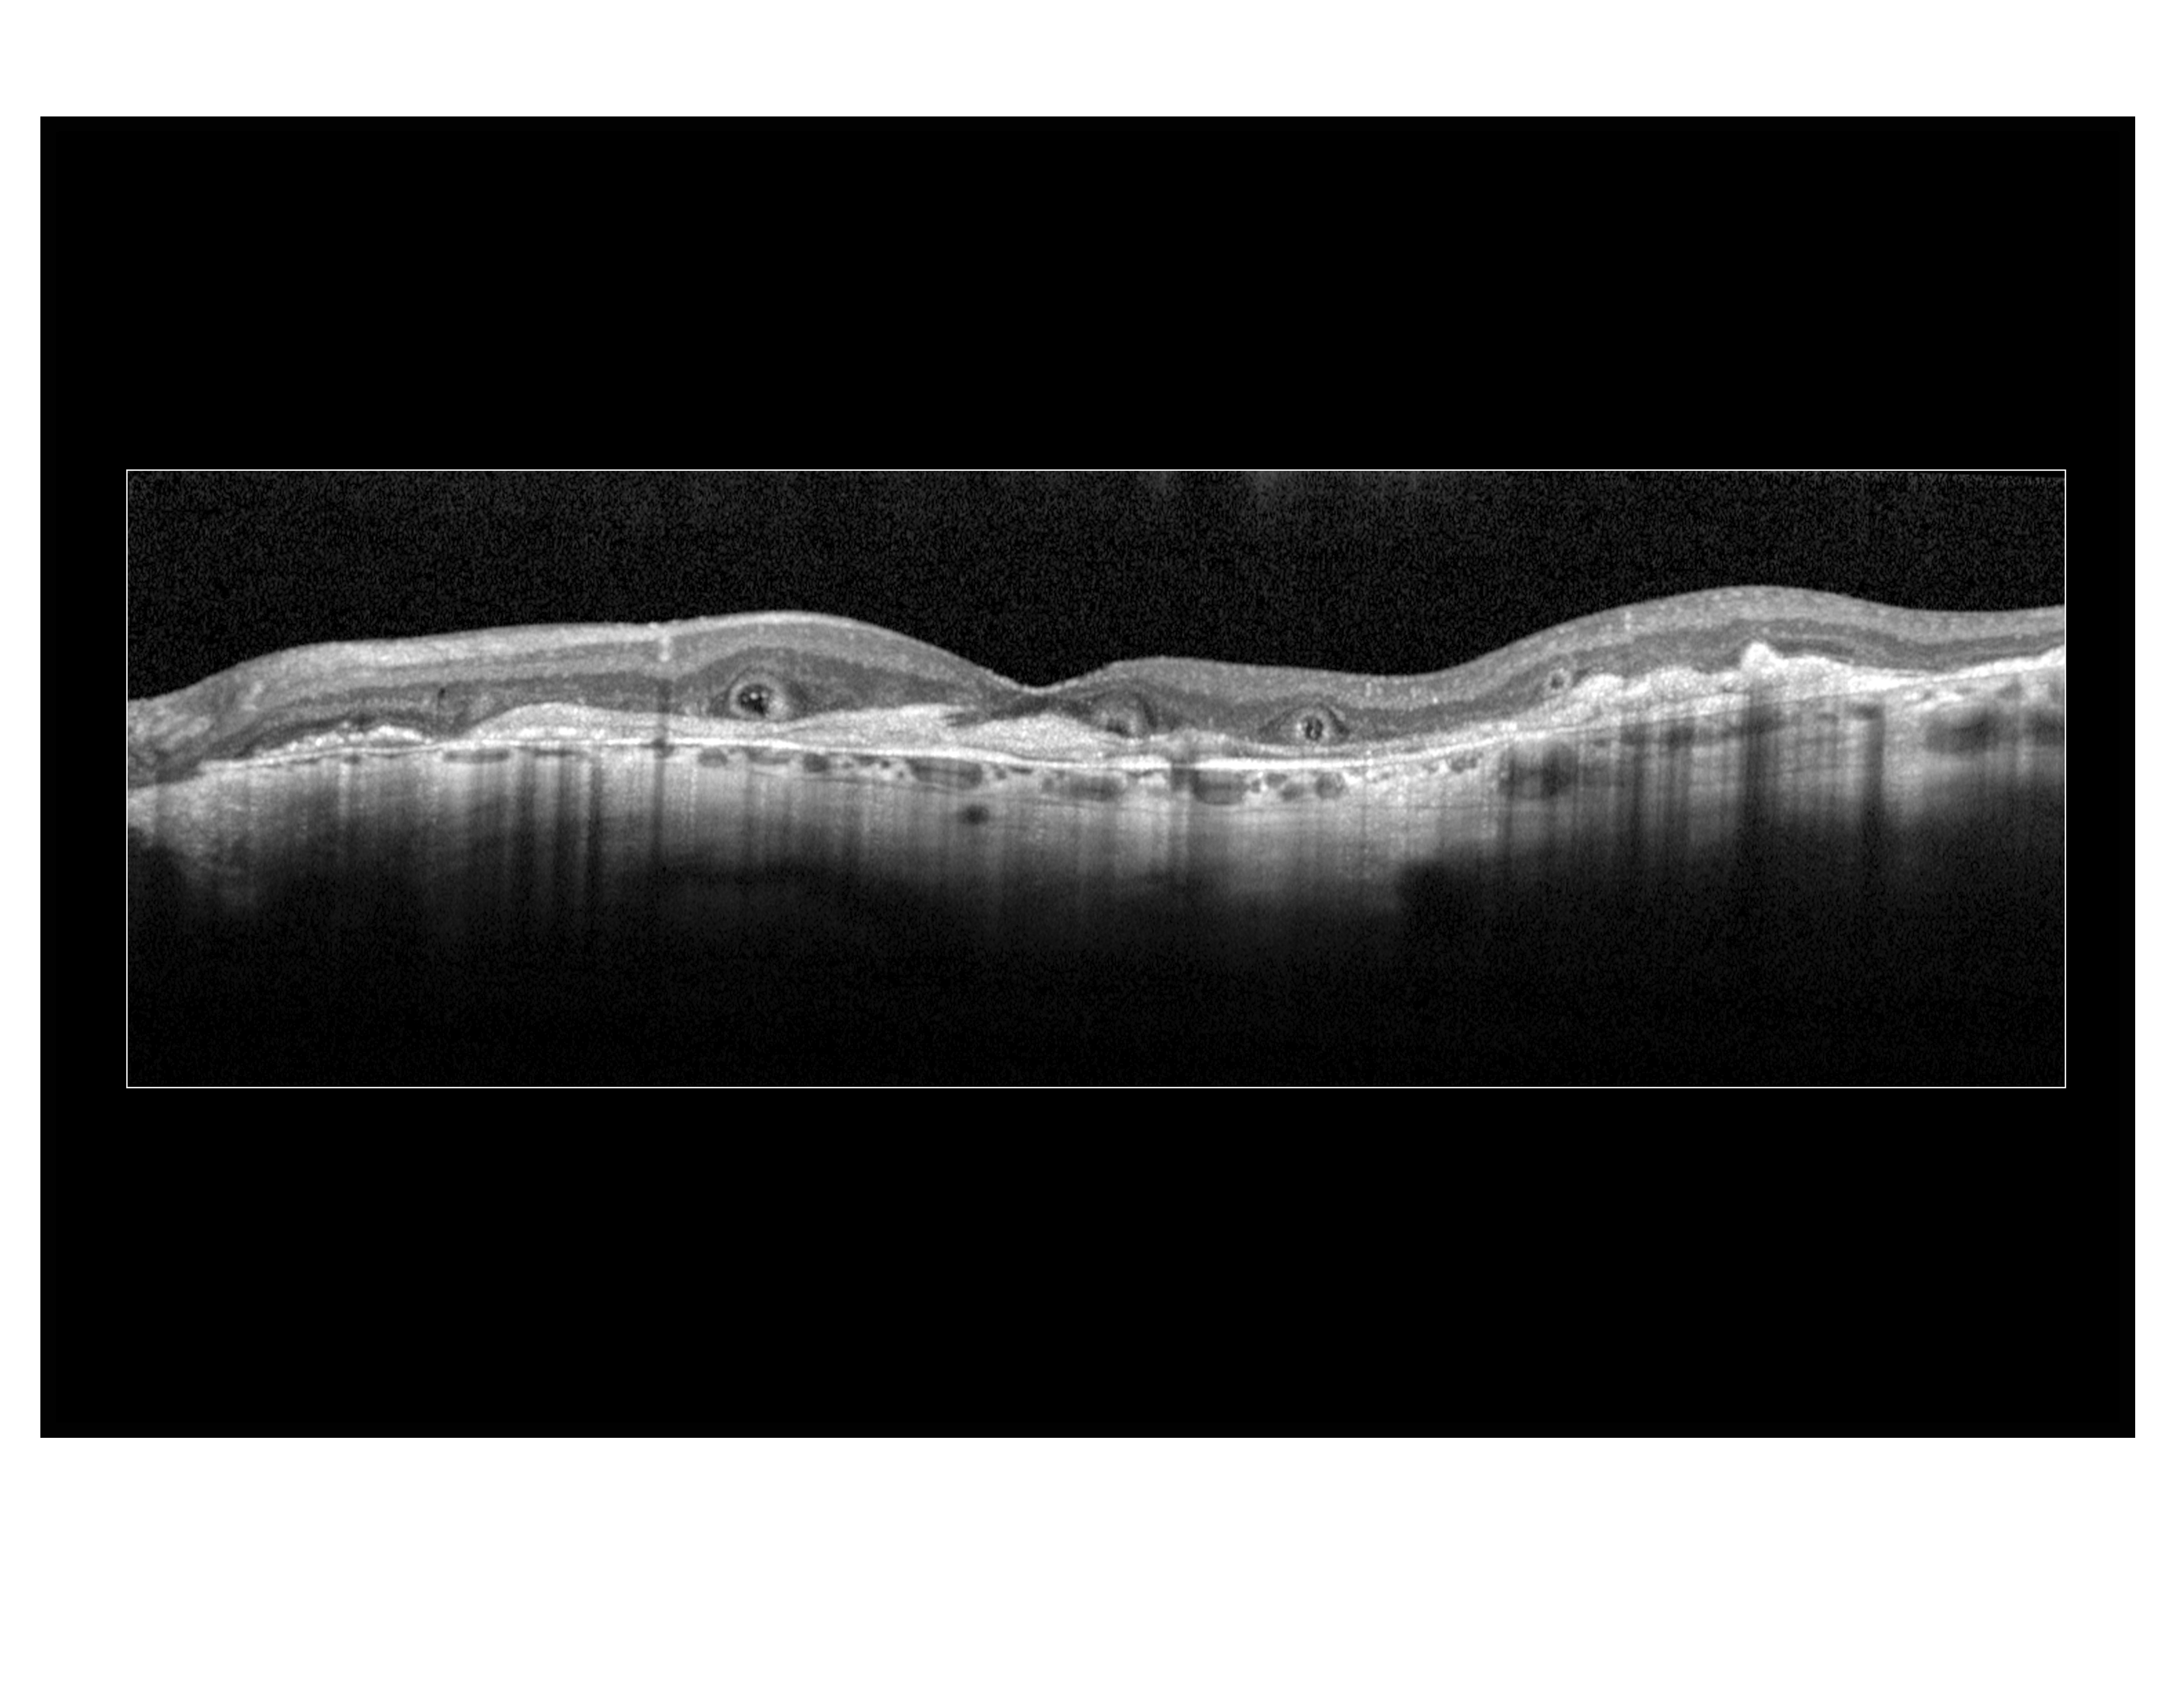

Outer Retinal Tubulation Presented by Megan Walsh, CRA, OCT-C This photograph received Honorable Mention in the category "Optical Coherence Tomography" and was displayed in the 2024 OPS Exhibit. Filed Under Retina OPS Photo